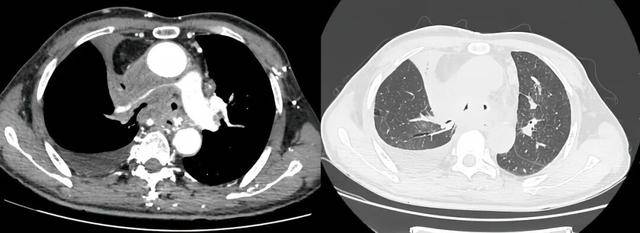

同期置入支架后狭窄明显改善

术后李先生的喘憋症状显著缓解:“那种窒息的恐惧感消失了,我终于能躺下睡个安稳觉了。”为平稳度过危险期,李大爷转至重症医学科接受高级别生命支持与治疗。经过短暂的术后观察,李先生各项生命体征平稳,活动耐量明显改善,顺利出院。